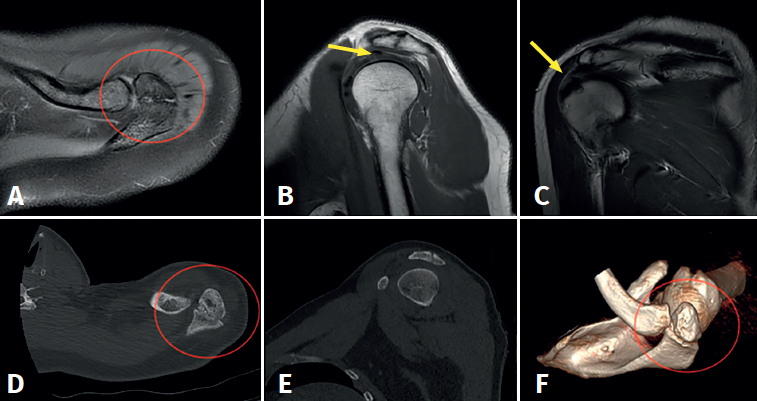

The basic imaging diagnostic explorations should include anteroposterior, axillary and scapular Y projection radiographs(Figure 1), with the axillary view being the most useful option in this regard(8). Magnetic resonance imaging (MRI) can identify additional disease conditions such as concomitant rotator cuff injury, for example(9). The presence of bone oedema in axial sections in fat-suppressed T2-weighted sequences is an expected sign in the MRI assessment of symptomatic os acromiale (Figure 2).

Figure 2. Preoperative magnetic resonance imaging and computed tomographic views showing deformation of the distal extremity of the acromion with the presence of an acromial ossicle of irregular morphology (images A, D and F, red circle) associated to incipient supraspinatus tendinopathy, with enhanced signal intensity of the tendon in the bursal surface (images B and C, yellow arrow).